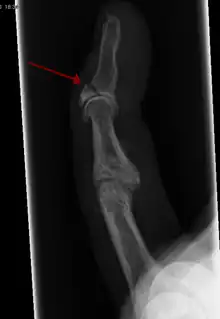

![]() In the fingertip. More images |

Linear fracture | Parallel to the bone's long axis | ||